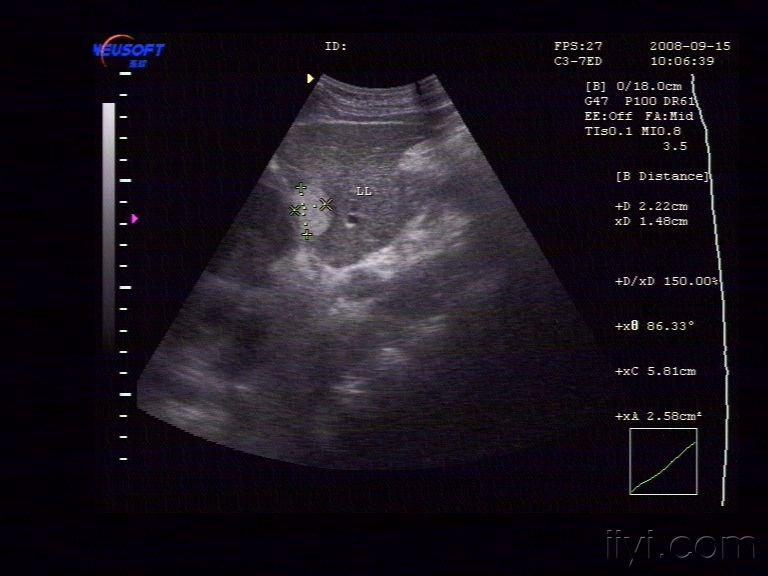

【贴图】肝脏血管瘤

体检发现左肝内一较强回声团,大小约为29X22X15mm,边界清,中央回声稍低。CDFI:未见异常血流信号